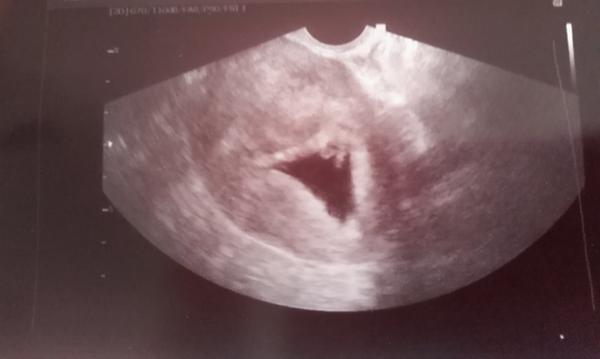

Ahojte, ideme z Brna, veľkosť zodpovedá týždňu 6+2 tt. Srdiecko bije. Prečo som spinila nevie, že on vidí ako všetko v poriadku. Tak sa tešíme🙂.

@darci17 ja som mala uzv o 8.30. Pred deviatou uz sme boli prec... ja som mala cestu iba necelu hodinu a mala som co robit s tym zaludkom !!! Ja som 6+3,tak to sme narovnako 🙂 mam strach tiez,hlavne lebo u dvojciat je vyssie riziko potratu, ale musim sa s tym potrapit a verit. Na negativne myslienky a zufanie bude dost casu,az by sa nieco stalo 🙂 predpokladam,ze tiez si doma PN ako my tu vsetky ostatne ?

Ja som bola vcera 6tt+3 a uz boli dve srdiecka :D